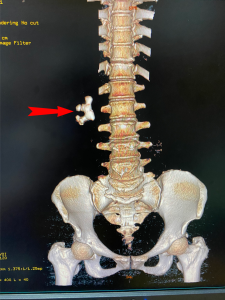

Người bệnh H.T.S 56 tuổi, ở xã Thương Long, huyện Yên Lập đến khám bệnh tại TTYT huyện Yên Lập, ở nhà người bệnh có dấu hiệu tiểu buốt một tuần nay, trong ngày thấy đau nhiều vùng dưới rốn, tiểu khó. Qua hình ảnh siêu âm và CT Scaner đã phát hiện người bệnh có sỏi san hô ở thận phải, kích thước lớn (20x31x40mm) gây ứ nước thận, có nguy cơ giãn đài bể thận, suy thận. Sau khi nghe bác sỹ giải thích, tư vấn người bệnh và người nhà đã thống nhất điều trị bằng phương pháp tán sỏi qua da bằng lazer.